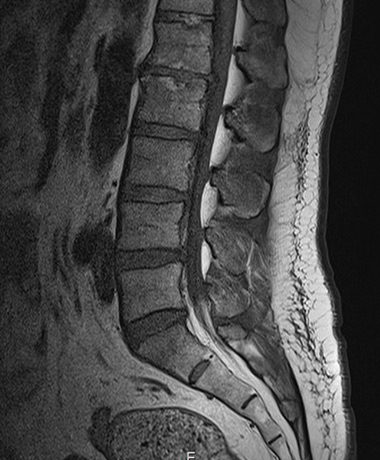

<h3>정확한 진단은 선명한 영상에서 시작됩니다</h3>

<div class="name">1.5T</div>

<div class="name">그린몰 3.0T</div>

<li>미세한 신경·인대·근육 등 연부조직까지 정밀한 촬영</li>

<li>선명한 해상도로 통증의 원인 및 미세 병변을 정확히 구분</li>

정확한 진단은 선명한 영상에서 시작됩니다

1.5T -

그린몰 3.0T

- 미세한 신경·인대·근육 등 연부조직까지 정밀한 촬영

- 선명한 해상도로 통증의 원인 및 미세 병변을 정확히 구분